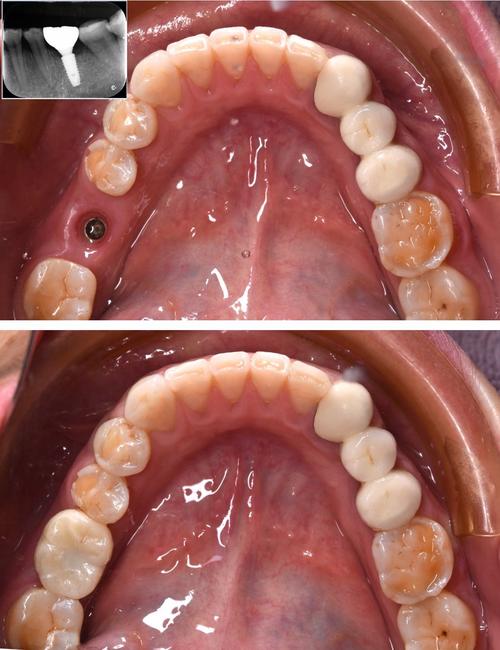

种植牙的成功,离不开精准的影像检查,现代口腔种植常用的影像技术包括根尖片、曲面断层片及锥形束CT(CBCT),其中CBCT因三维成像、高分辨率、辐射剂量可控等优势,已成为种植术前的“金标准”,拍片的核心作用体现在以下方面:

精确测量骨量,制定安全植入方案

CBCT可三维重建牙槽骨形态,清晰显示骨的高度、宽度、密度,以及骨内凹陷、缺损区域,医生通过软件分析,可精确计算种植体的直径、长度,选择合适的种植体型号,确保种植体植入后周围有至少1-2mm的骨壁包裹,提供初期稳定性,对于牙槽骨严重萎缩的患者,可通过CBCT判断是否需要植骨、骨增量手术的量及范围,避免盲目种植。

定位重要解剖结构,规避手术风险

CBCT能清晰显示下牙槽神经管、上颌窦底、颏孔、鼻腭管等解剖结构的位置及走行,下颌后牙区的种植体需距离下牙槽神经管至少2mm,上颌后牙区的种植体需距离上颌窦底至少1mm,CBCT可帮助医生精准标记安全植入范围,避免神经损伤和上颌窦穿孔,对于邻牙牙根倾斜、弯曲的情况,CBCT可明确牙根形态,确保种植体与牙根间保持足够距离(至少1.5mm)。